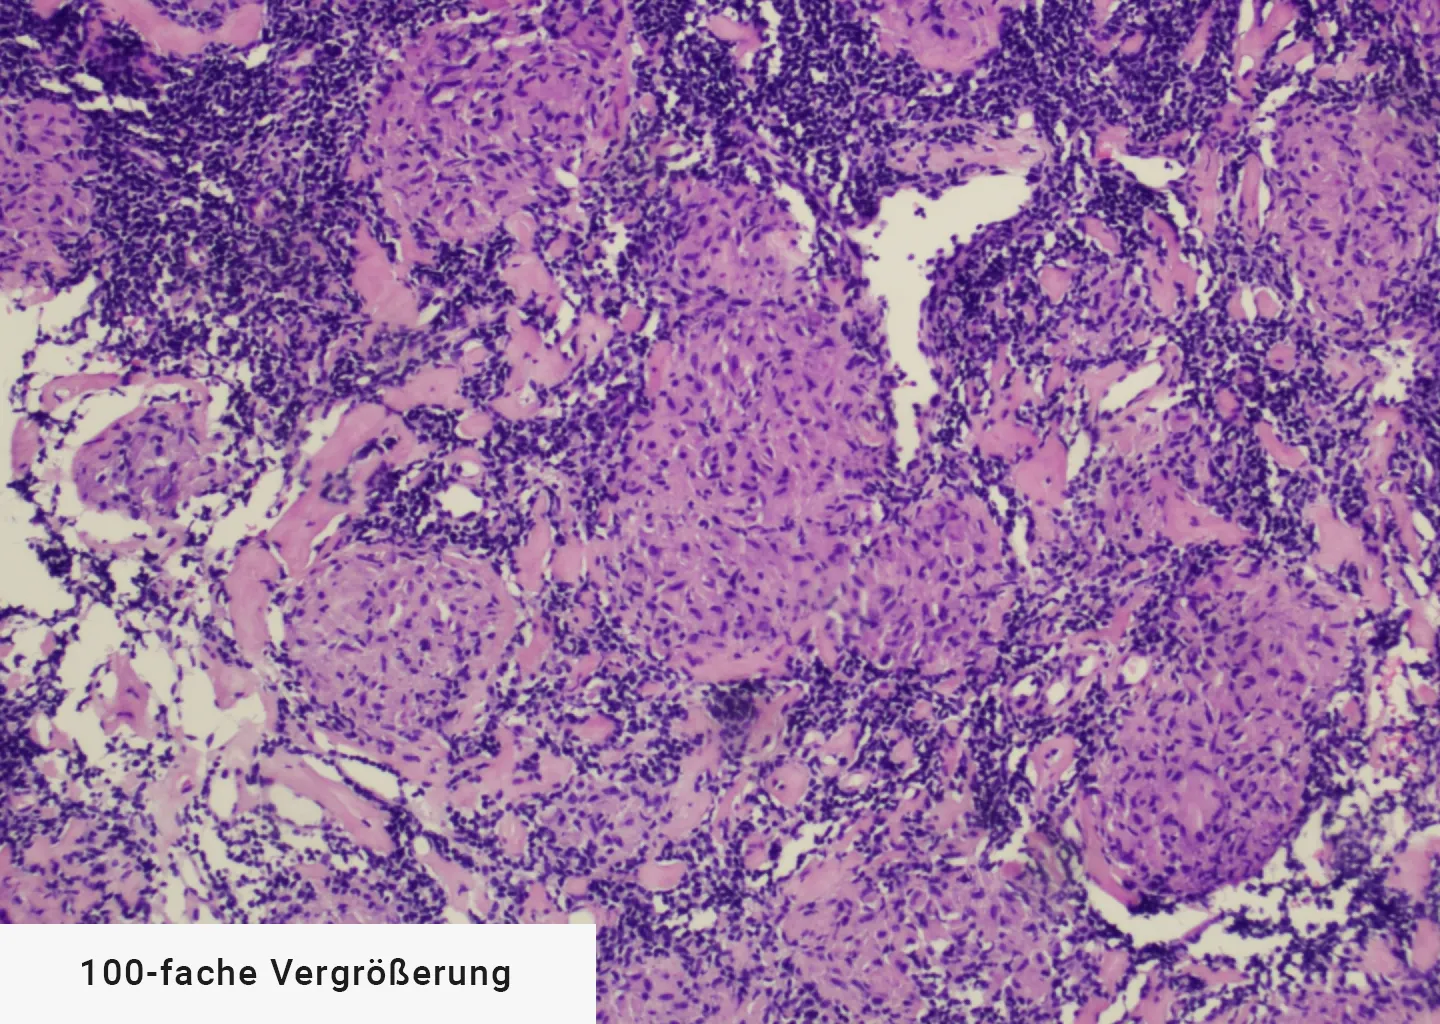

Der Altersgipfel liegt zwischen dem 30. und 40. Lebensjahr, wobei typischerweise ein Epitheloidzellgranulom ohne zentrale Nekrose vorliegt. Die Prävalenz (Anteil der erkrankten Personen an der Gesamtpopulation) liegt bei etwa 40 pro 100.000 Einwohnern, wobei die Inzidenz (die Anzahl neuer Krankheitsfälle) circa 10 pro 100.000 Einwohnern beträgt.

Man sieht die klassischen Epitheloidzellgranulome, die bei Sarkoidose vorkommen: Es handelt sich im konkreten Fall um den mediastinalen Lymphknoten Nr. 7, welcher mit einem transbronchialen Kryobiopsat gewonnen wurde.